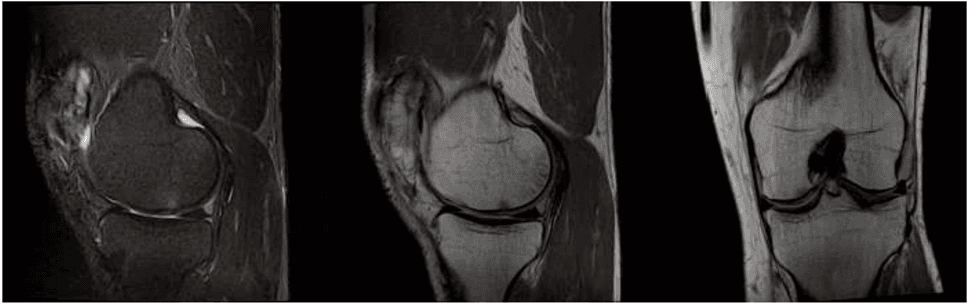

Ogni caso di artrosi è unico e richiede un'analisi meticolosa prima di procedere con qualsiasi intervento. Presso la nostra clinica a Milano, il percorso inizia con una visita specialistica approfondita supportata da esami diagnostici per immagini, come risonanze magnetiche o ecografie ad alta risoluzione. Questa fase è cruciale per determinare il grado di usura articolare e l'idoneità del paziente alla medicina rigenerativa.